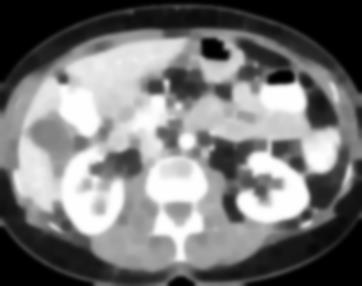

Due to the constraints of the imaging device and high cost in operation time, computer tomography (CT) scans are usually acquired with low intra-slice resolution. Improving the intra-slice resolution is beneficial to the disease diagnosis for both human experts and computer-aided systems. To this end, this paper builds a novel medical slice synthesis to increase the between-slice resolution. Considering that the ground-truth intermediate medical slices are always absent in clinical practice, we introduce the incremental cross-view mutual distillation strategy to accomplish this task in the self-supervised learning manner. Specifically, we model this problem from three different views: slice-wise interpolation from axial view and pixel-wise interpolation from coronal and sagittal views. Under this circumstance, the models learned from different views can distill valuable knowledge to guide the learning processes of each other. We can repeat this process to make the models synthesize intermediate slice data with increasing inter-slice resolution. To demonstrate the effectiveness of the proposed approach, we conduct comprehensive experiments on a large-scale CT dataset. Quantitative and qualitative comparison results show that our method outperforms state-of-the-art algorithms by clear margins.